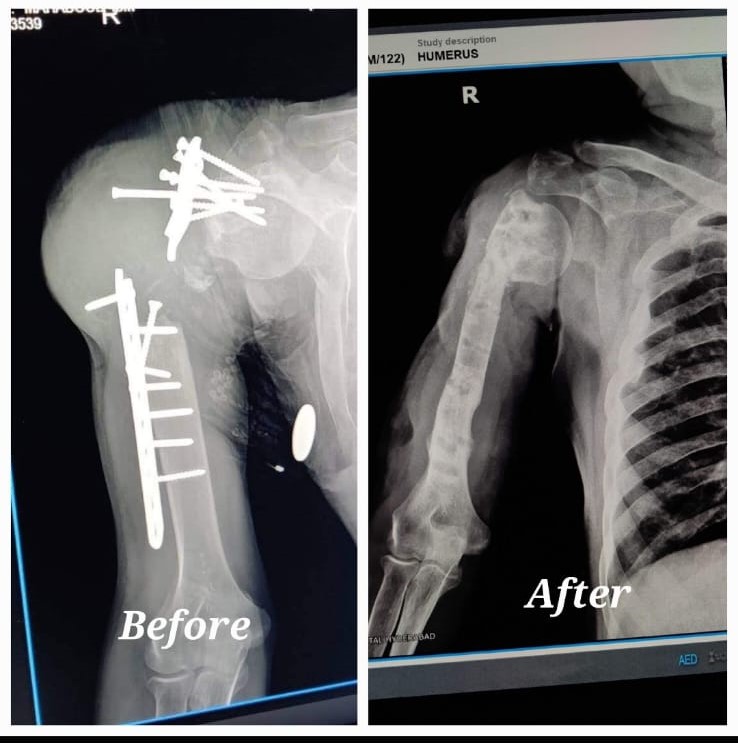

Gap nonunion and failed implant management with Bone Transport